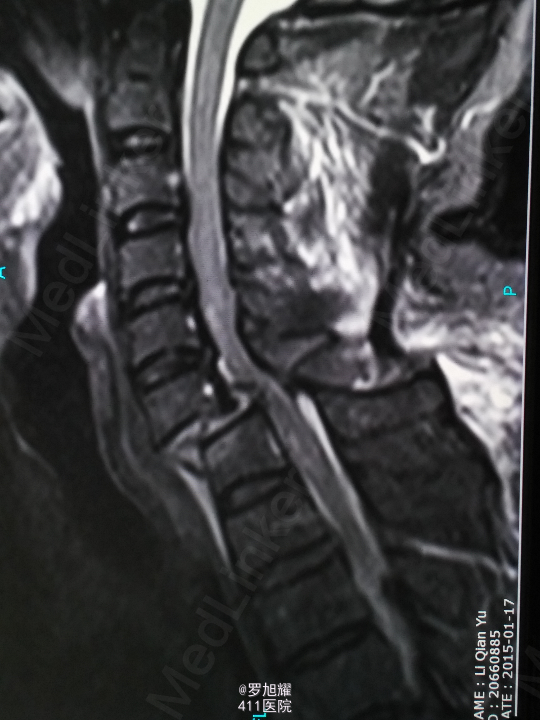

查体:双上肢前臂及以远感觉丧失,躯体自第二肋间平面以下感觉丧失。耸肩可,双侧三角肌、肱二三头肌肌力2级,腕关节屈伸、旋转及各指肌力0级。腱反射阴性,但球海绵体反射已经阳性。影像学检查示颈椎骨折脱位伴颈髓损伤。

诊断:颈6/7骨折脱位伴高位截瘫。处理:立即甲强龙冲击、脱水、保胃、营养神经治疗。首选治疗方案是颅骨牵引复位后前路融合固定,较后路稳定,出血也少,和家属谈话后开始颅骨牵引复位,4kg起步,每半小时增加1kg直至14kg,调整颈椎屈伸位,再加用手法牵引仍不能复位。改用备选方案,急诊行后路切开减压撬拨复位内固定,术后瘫痪症状部分改善。随访3月双上肢前臂及手部感觉恢复,仅双手掌尺侧及小指感觉障碍,双侧三角肌、肱二三头肌肌力4-5级,腕关节屈伸、旋转肌力左侧3级,右侧3-4级,但各指肌力仍0级。